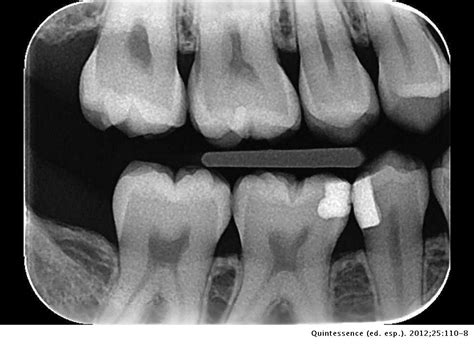

Radiografía Interproximal o Aleta de Mordida

En esta clase de radiografías dentales, la imagen se toma dentro de la boca del paciente. Se utilizan sobre todo para identificar casos de caries interproximales (entre los dientes del paciente) o problemas en las raíces de los dientes. Aunque no sea lo ideal, para facilitar su realización, a veces se le pide el paciente que sea él mismo el que sujete la placa radiológica.

La placa se coloca a lo largo de la mordida del paciente, para obtener una imagen completa de las coronas dentales del paciente. La radiografía dental interproximal sirve, principalmente, para detectar caries y evaluar el estado de la corona y del tejido periodontal, así como detectar posibles alteraciones pulpares.